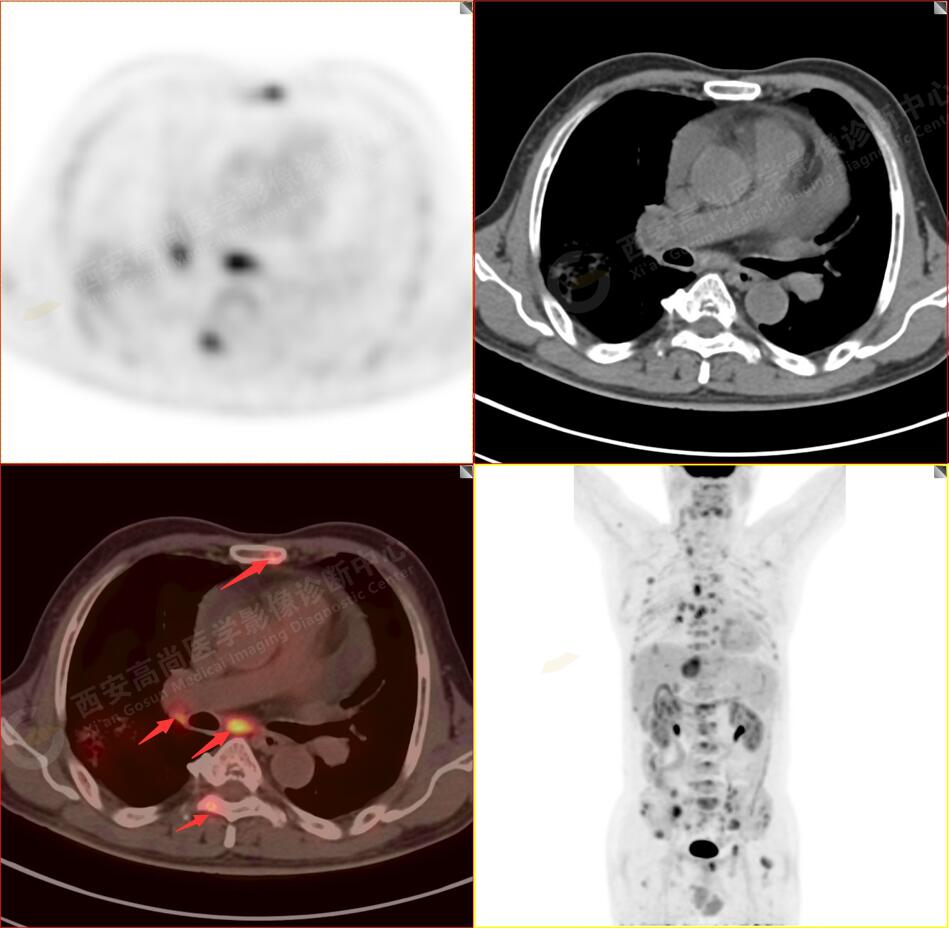

PET/CT圖像

2.以下為全身多發(fā)轉移灶

3.右側頸部(Ⅱ-Ⅴ區(qū))、右側腋窩區(qū)、右側肺門及縱隔(1R、1L、2、4、6、7組)、肝門區(qū)多發(fā)腫大淋巴結,呈不同程度異常增高,均考慮為淋巴結轉移。